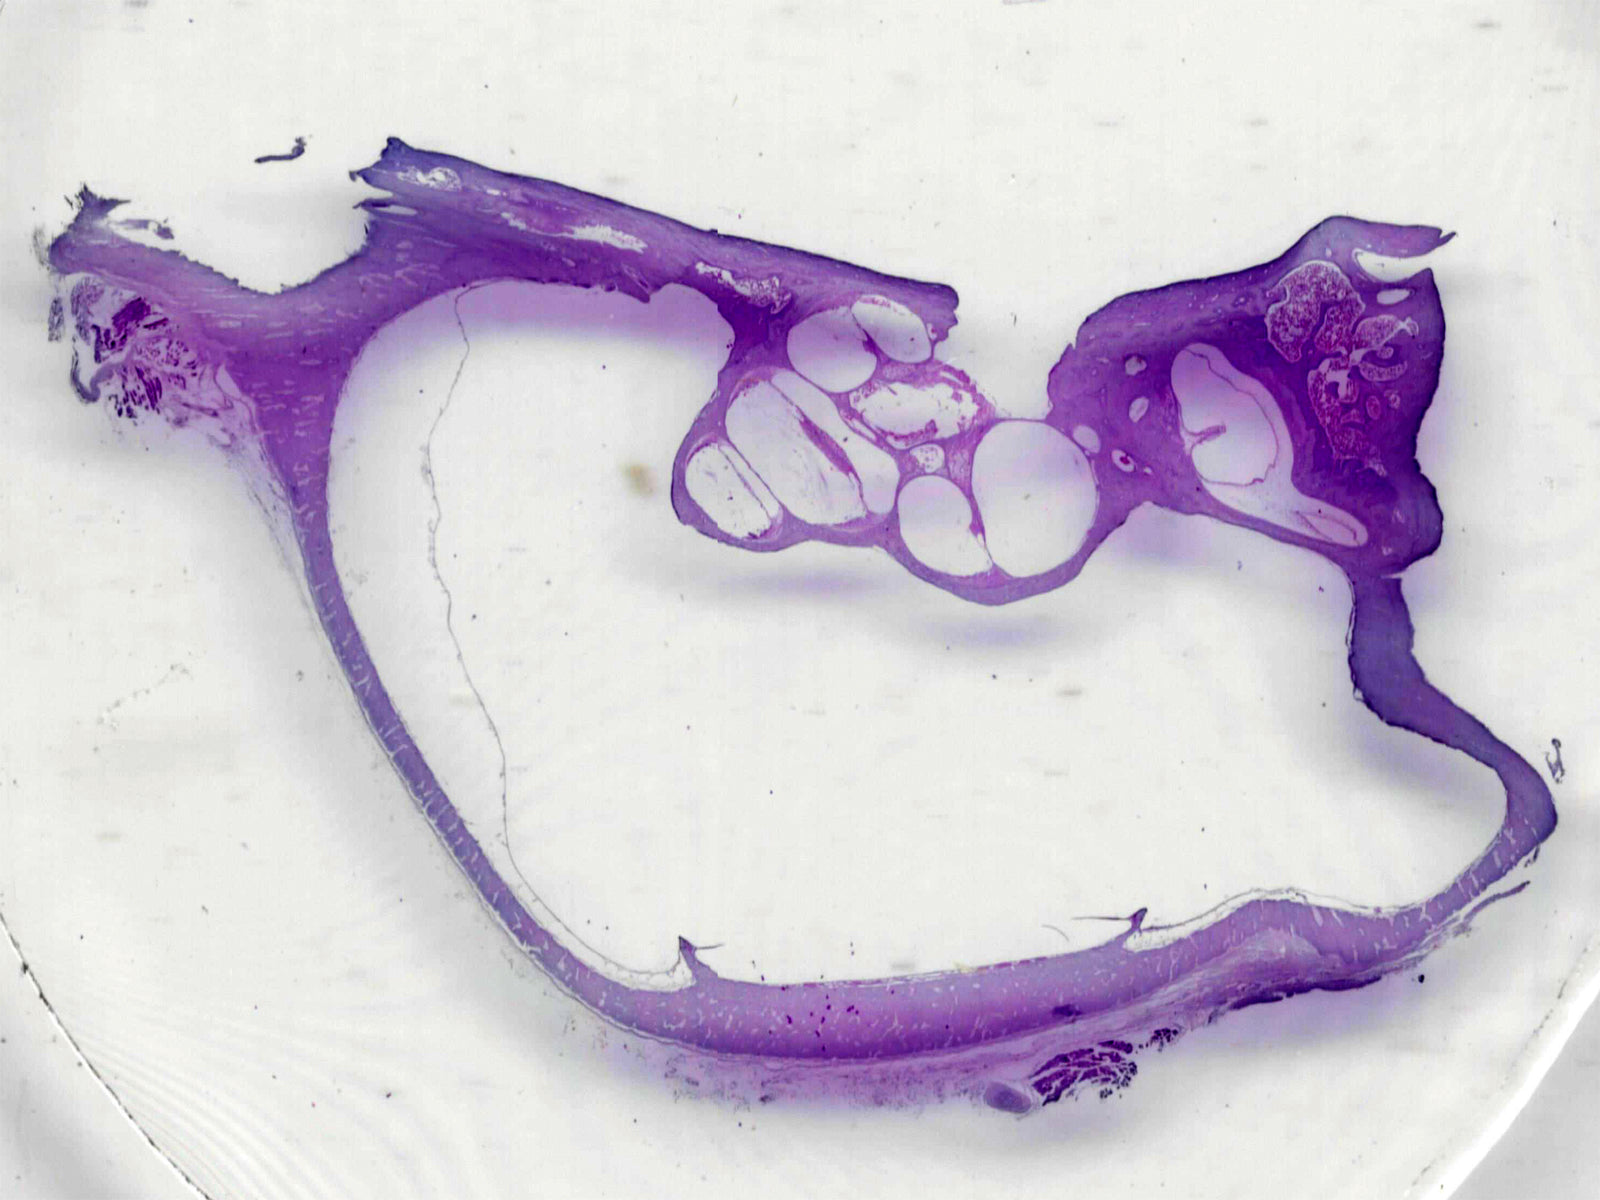

We carry a vast selection of prepared microscope slides. They can be closely investigated under a microscope to explore botany, fungi, histology, monera, pathology, protists, and zoology.